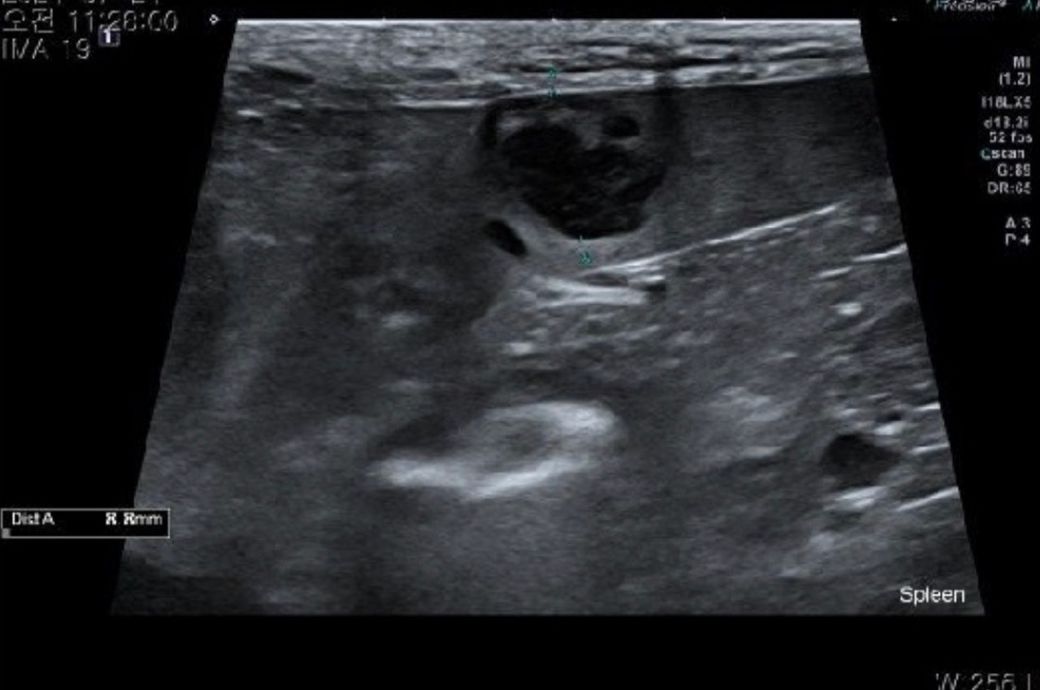

비장은 절제 수술 하기로 했습니다 .초음파상 혹들 어때보이나요ㅠㅠ?신장 물혹은 커서 수술할 때 물 빼도 무리는 안될까요????

비장쪽에도 종양이 생긴 것 같은데 해당 부분은 CT촬영 후 전이소견 여부를 제대로 확인 후 수술하시는 것을 권유드립니다.